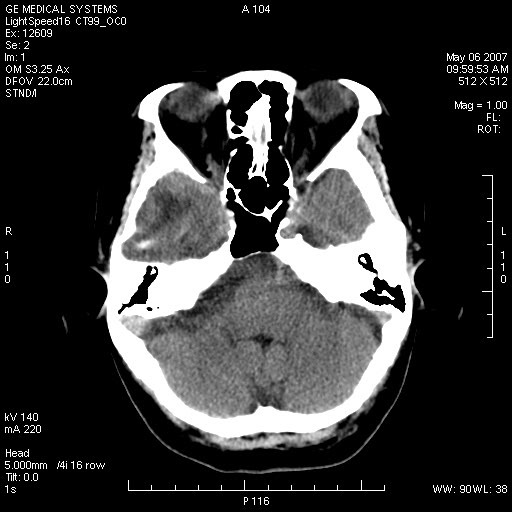

女,60岁,头痛6~7天。

右颞叶巨大高低混杂密度肿块,病灶内可见多发条块状钙化影,占位效应明显,中线结构显著左偏,肿块周围水肿明显,临近颅骨吸收变薄,边缘光整,考虑1少枝胶质瘤2脑膜瘤3转移瘤4室管膜瘤5淋巴瘤6三叉神经瘤(多多益善)合并镰下疝

右颞叶分叶状稍高密度灶,占位效应明显,外周见水肿带,其内见点条样高密度钙化灶,临近颅骨变薄,考虑:脑膜瘤,少突胶质瘤。

右额、颞叶巨大高低混杂密度肿块,病灶内可见多发条块状钙化影,占位效应明显,中线结构显著左偏,肿块周围水肿明显,临近颅骨吸收变薄,边缘光整。

考虑:1、少枝胶质瘤;

2、脑膜瘤?

3、镰下疝;

4、建议增强扫描进一步检查。